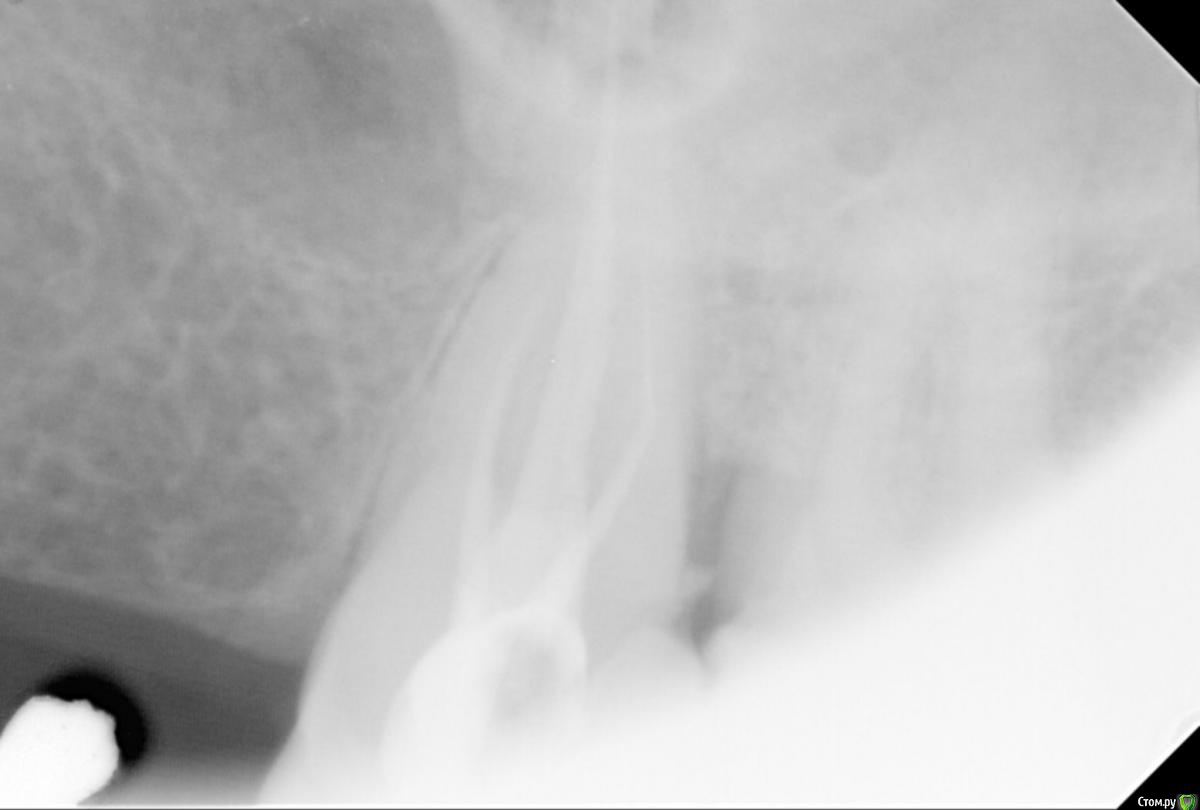

anvladd Опубликовано 3 января, 2017 Поделиться Опубликовано 3 января, 2017 Однозначно переделывать,в дистальном щечном канале сломанный инструмент. Ссылка на комментарий

DmitrySH Опубликовано 3 января, 2017 Поделиться Опубликовано 3 января, 2017 Инструмент в 6 зубе есть. Я бы сейчас не пытался достать, т.к. инструмент за изгибом корня и создание доступа потребует достаточно инвазивной работы. Нужно 7 зуб на витальность проверить. и сделать КТ на предмет еще одного канала в 6 зубе. Ссылка на комментарий

sugaka30 Опубликовано 4 января, 2017 Автор Поделиться Опубликовано 4 января, 2017 (изменено) Инструмент в 6 зубе есть. Я бы сейчас не пытался достать, т.к. инструмент за изгибом корня и создание доступа потребует достаточно инвазивной работы. Нужно 7 зуб на витальность проверить. и сделать КТ на предмет еще одного канала в 6 зубе. Спасибо за ответ ! 7 ка пломбированна делал недавно Эод результат 46 и 47 Горячее и холодное она не чувствует и нажим не болезненный По поводу 6 ки вчера только узнал что врач запломбировал канал дистально прищечный Форфенановой пастой Наверное понял что инструмент сломан или что не до конца его прошел Основной канал гутаперча НЕТЕРМОФИЛЬНАЯ с конасоном Может это форфенан дает такой эффект Изменено 4 января, 2017 пользователем sugaka30 Ссылка на комментарий

sugaka30 Опубликовано 7 января, 2017 Автор Поделиться Опубликовано 7 января, 2017 И скажите все таки есть перфо материала в гайморову или пронесло? Ссылка на комментарий